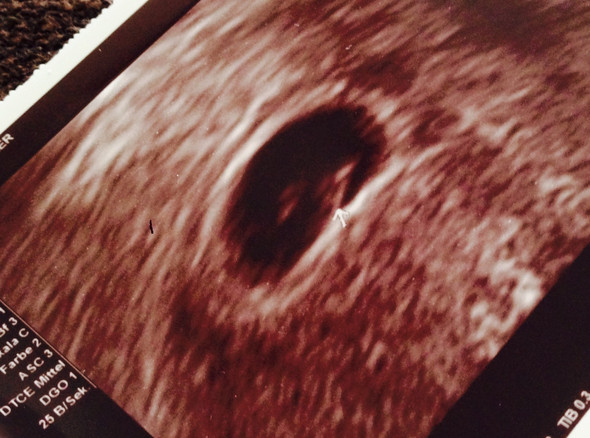

Und auch kein Blick in irgendwelche Statistiken die besagen wie viele der ursprünglichen Zwillingsschwangerschaften mit der Geburt von nur einem Säugling enden. Zwillinge kann man schon ab der sechsten Schwangerschaftswoche erkennen aber in diesem frühen Stadium kommt es leider oft vor dass ein Embryo stirbt. Heute bei 7 SSW 6 wurde festgestellt dass der eine Zwilling nicht weiter gewachsen ist und nun abgeht.

Laut einer statistischen Regel nach Helling kommt eine Zwillingsgeburt auf 85 Einfachgeburten 1. Stirbt ein Zwilling im Mutterleib schon sehr früh verschmilzt er meist fast spurlos mit der Plazenta. Hallo Zusammen war mit Zwillingen schwanger.

Ein Zwilling gestorben in 7. Jedes zehnte Baby hat sein Leben zu zweit begonnen.

Die Zahlen schwanken zwischen 30 und 70. Jedes zehnte Baby hat sein Leben zu zweit begonnen. Doch im Verlauf der Schwangerschaft stirbt ein Zwilling im Mutterleib. Hallo Zusammen war mit Zwillingen schwanger. Gestörtes Bindungsverhalten und ein erhöhtes Risiko für. Sowas passiert leider häufiger. Für Frauen beginnt diese Phase meist in den letzten Wochen der Schwangerschaft. Laut einer statistischen Regel nach Helling kommt eine Zwillingsgeburt auf 85 Einfachgeburten 1. Wie oft stirbt ein zwilling in der frühschwangerschaft Zwillinge Was bei einer Zwillingsschwangerschaft wichtig is Zwillings- und Mehrlings-Mamas leiden in der Frühschwangerschaft oft stärker unter Übelkeit als Frauen die nur ein Kind erwarten.